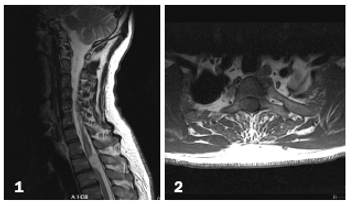

Spinal problems include epidural abscess, paravertebral muscle atrophy, Chiari I malformation, osteomyelitis/discitis, diastematomyelia, spinal compression, spinal tuberculosis.